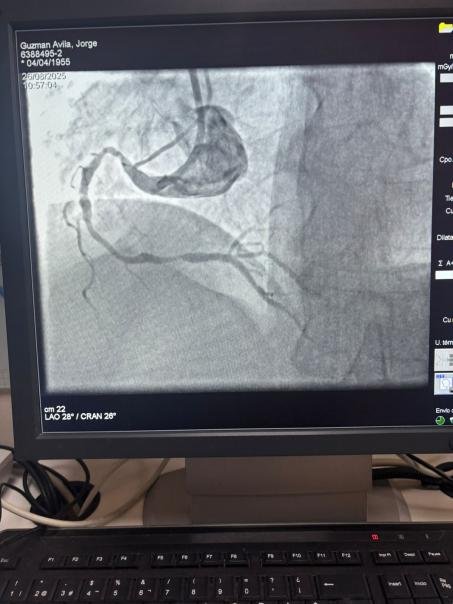

Jesteśmy dumni, że możemy podzielić się niezwykłym przypadkiem ze Szpitala Sótero del Río w Chile, gdzie dr Martín Valdebenito z powodzeniem leczył silnie zwapnione uszkodzenie w prawej tętnicy wieńcowej (pierwsza krzywa) za pomocą naszego systemu cewnika Vesscrack Coronary IVL Balloon Dilatation.

Procedura osiągnęła znakomite wyniki, przy czym zwapniały obszar skutecznie pękł i przywrócono przepływ w naczyniu. To kolejny kamień milowy w rozszerzaniu globalnego dostępu do zaawansowanych rozwiązań dla złożonych zwapnień wieńcowych.

Porównanie obrazów angiograficznych przed zabiegiem i po zabiegu wyraźnie pokazuje znaczący wpływ kliniczny naszej technologii IVL.